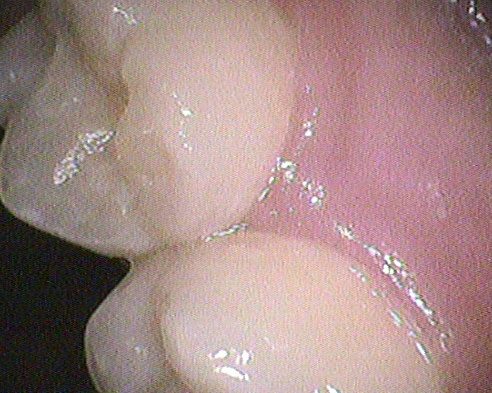

◎クリーニング後